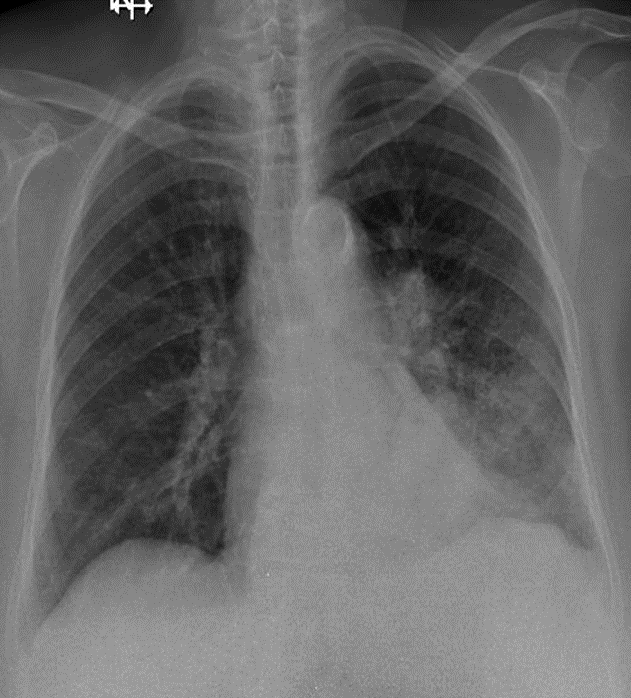

1-Thâm nhiễm phế nang lan tỏa thùy dưới phổi (T)=> Viêm phổi 2-Cung động mạch chủ đóng vôi